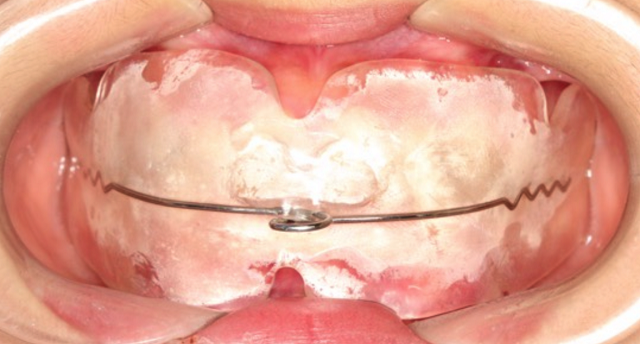

黃丞一副主任醫(yī)師仔細(xì)檢查后發(fā)現(xiàn),孩子的門(mén)牙突出,上頜牙弓特別狹小,整排牙齒都非常不整齊。

“當(dāng)腺樣體組織異常增生肥大時(shí),就會(huì)堵塞氣道,導(dǎo)致長(zhǎng)期張口呼吸,還可影響頜面部發(fā)育,形成特殊的腺樣體面容。腺樣體面容是指由于腺樣體肥大導(dǎo)致牙齒不整齊并且向外凸出,形成齙牙,上嘴唇也會(huì)變厚,腭骨高拱,還伴有表情呆滯等情況。”黃丞一醫(yī)生說(shuō)。

雖然當(dāng)時(shí)接診時(shí),小林的腺樣體腫大已經(jīng)存在了一段時(shí)間,不過(guò)幸好發(fā)現(xiàn)及時(shí)。根據(jù)黃醫(yī)生的建議,小林及時(shí)到耳鼻喉科做了腺樣體摘除術(shù),并且認(rèn)真地進(jìn)行肌功能訓(xùn)練,對(duì)已經(jīng)凸出的牙齒進(jìn)行矯正。

第三,如果已經(jīng)發(fā)生了口腔錯(cuò)合畸形,就需要根據(jù)不同的錯(cuò)合畸形類(lèi)型進(jìn)行功能性矯正和后期的固定矯正了。